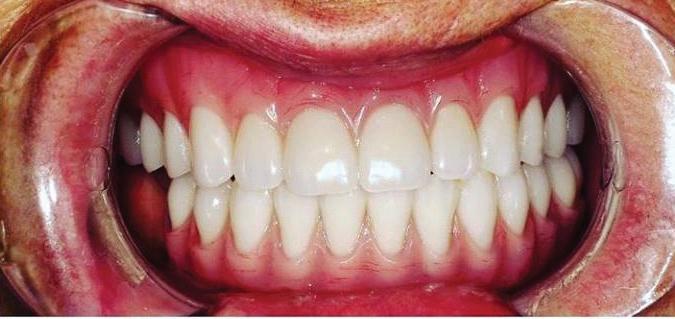

Submitted By Sivakumar Sreenivasan, DMD, MDS Dental Implant Center of Rockville

Can just four implants replace all of the teeth on the top or the bottom of your mouth? Thanks to advances in dental implant technology, that answer is a resounding yes.

Tooth loss is extremely common among adults, especially as we age. Rather than living with the discomfort and hassles of dentures, many people are opting for what is called “all-onfour” dental implant restoration.

An implant is a small titanium

screw that fits inside your jawbone and replaces the root-part of a missing tooth. Minor surgery is required to insert the implants. Once the implant is in place, a crown is attached to give you a highly realistic-looking and functional prosthetic tooth.

You do not need a dental implant for each and every one of your missing teeth. All you need is four precisely placed implants on the top of your mouth, and four on the bottom, to restore your full smile. That’s the beauty of the all-on-four. And because the implant is made of titanium, it has the unique ability to fuse to living bone and function as part of it. So eventually, the dental implant becomes part of the jawbone and serves as a strong, longlasting foundation for your new teeth.

Besides ensuring that your implants are permanently fixed in place, this bone fusion has another important benefit: it prevents future bone loss in the jaw. This helps to maintain a more youthful facial structure – and better

Please see “All-On-Four,” page 62